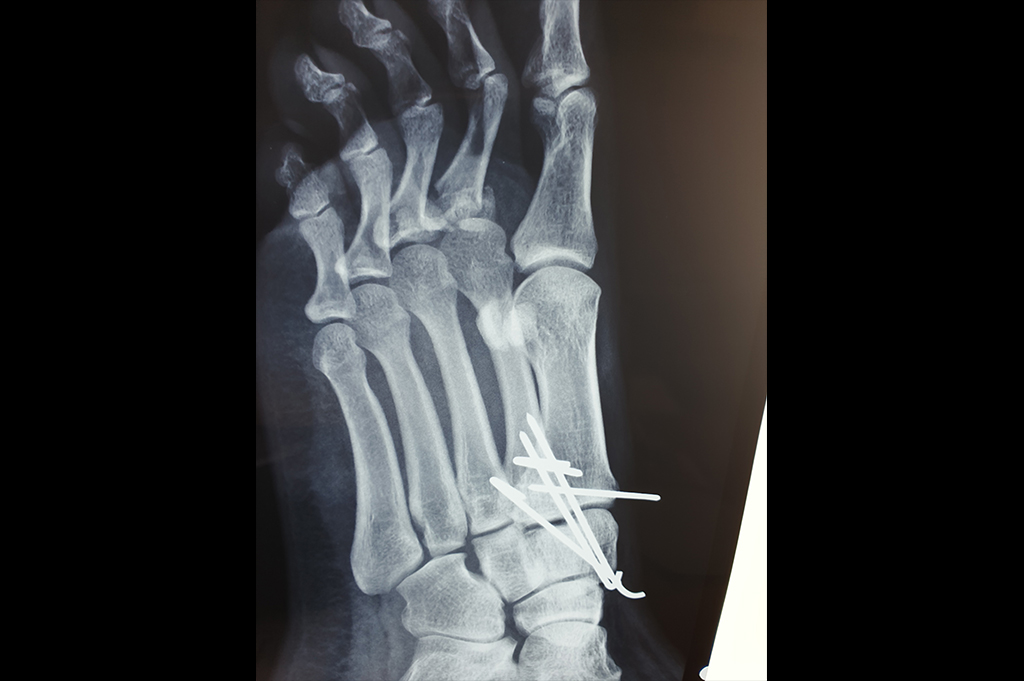

Metarsals with dislocations Lisfranc